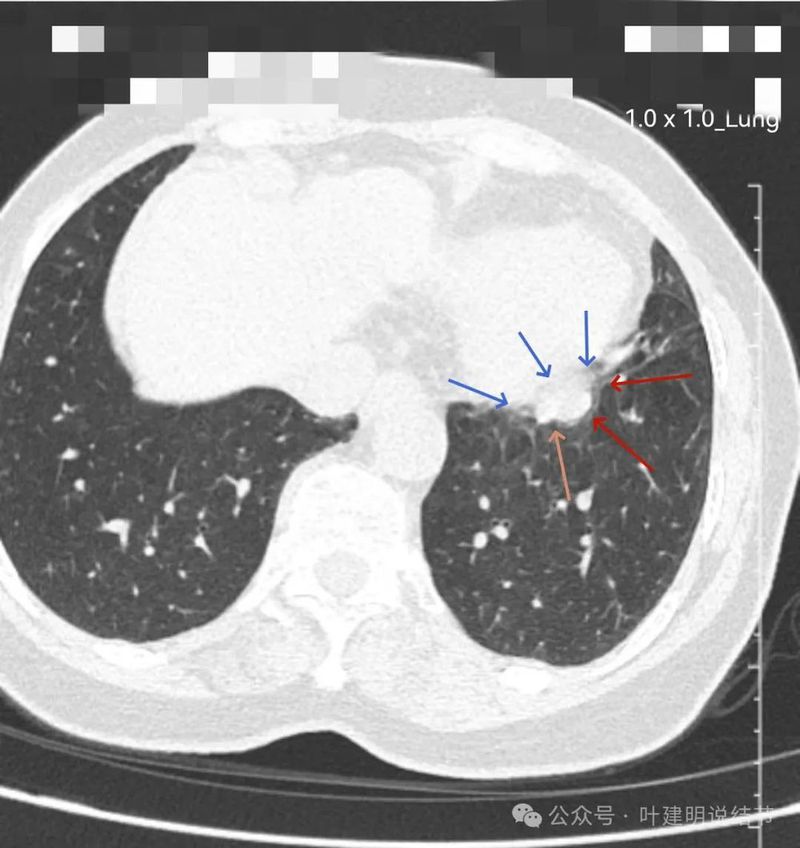

边界与轮廓清。

上图显得膨胀感欠了点,但分叶与表面不平是明显的。

边比较为平直,密度仍实。

感觉两处不同的中心,如果连续层面看,应该是病灶不平的关系,与膈肌间仍有间隙,密度是实性的。

边缘区域的样子。

较为边缘部分的纵隔窗样子。